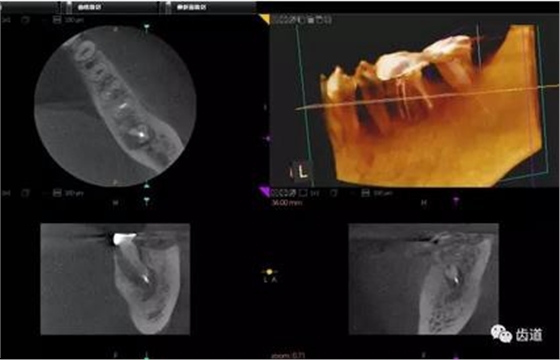

CBCT在牙槽骨外科手術(shù)中,通過立體影像可以全面了解牙齒周圍的解剖結(jié)構(gòu),牙根的位置,下頜神經(jīng)管的走向和范圍,上頜竇底的位置及上下牙牙根與上頜竇的關(guān)系,下牙牙根與下頜神經(jīng)管的位置關(guān)系,手術(shù)時(shí)就會“有的放失”,采用更加安全的方法,避免損傷上頜竇和下牙槽神經(jīng)。

1、上頜尖牙阻生

上頜尖牙埋伏阻生在CBCT中的影像